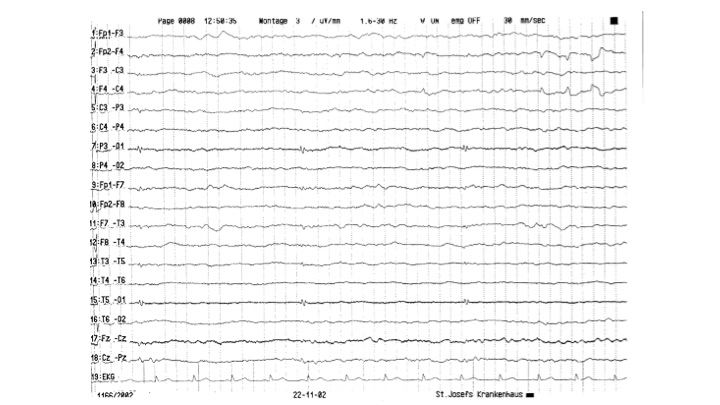

Artefakte im EEG | 43.65 zurück | weiter